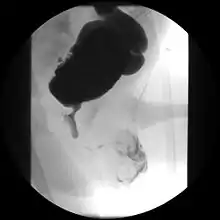

Tomografia de uma obstrução infravesical, por válvula de uretra.